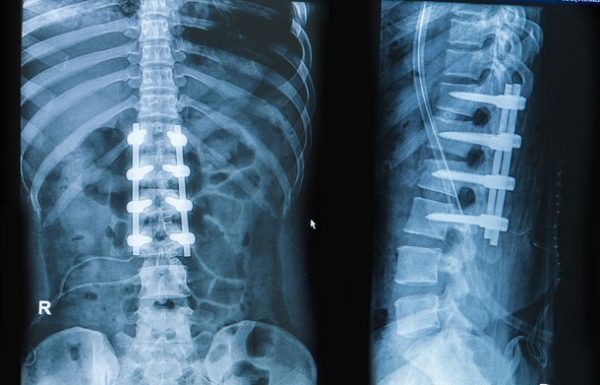

Spondylodese: Die „Wirbelversteifung“ hilft selten

AllgemeinEine Wirbelsäulenversteifung gilt bei gravierenden Rückenschmerzen oftmals (immer noch!) als Ultima Ratio.

In manchen Fällen ist die Operation oftmals unabdingbar (nach Wirbelbrüchen usw.), jedoch stehen die Risiken in keinem vernünftigen…